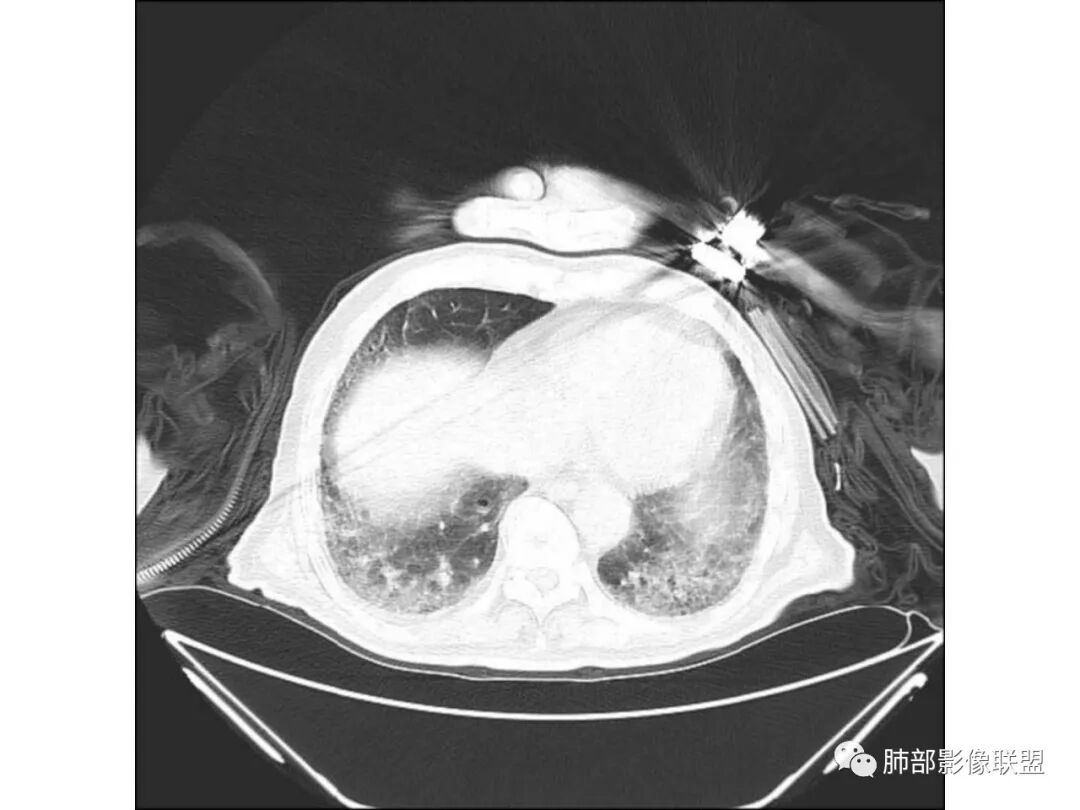

老年男性,咳嗽气喘10天,双肺明显肺气肿,右上肺叶实变,内见大量空洞及囊腔样改变(部分为支气管扩张),实变区周围表现为网格样改变,有明显的小叶间隔增厚,边界似清非清,支气管走行僵硬,有枯树枝样改变,双下肺胸膜下小叶间隔增厚明显,边缘相对模糊,综合考虑如下:1、粘液腺癌可能大(枯树枝样改变,边界似清非清,小叶间隔增厚符合)。2、结核,右上肺似像干酷样改变,内有空洞及支扩样改变支持,但下肺及左肺无相关支气管播散的小叶中心结节及树芽,不支持,临床病症不支持,只有咳嗽,喘气,无咳痰及结核中毒症状。当然结核是妖,需要结合痰检及结核相关指标进一步明确。3、肺克,虽有10年糖尿病史,但肺部只有右肺改变明显,无胸膜下脓肿表现,无脓毒栓表现,临床症状也不支持。4、其他感染?双下肺胸膜下病灶边缘模糊,不完全除外,需要结合临床炎性指标分析。

双胞胎的结核与粘液腺癌

粘液腺癌和干酪性肺炎鉴别:

1、结核干酪空洞常很干净,很彻底,而粘液腺癌空洞内有液性成份,不干净。

2、支气管:干酪样肺炎内的支气管破坏的,扩张的,粘液腺癌小支气管多狭窄的堵塞的,大支气管较完好,枯枝征。

3、增强扫描很重要,增强后,结核的坏死很彻底,很少异常强化,(鳞癌也类同)。而粘液腺癌血管常显影,有时是毛糙的,整体密度偏低,哟其实纵膈窗。

4、症状,粘液腺癌白痰为主。

5、这样的结核灶,其实痰检出抗酸杆菌阳性的几率常较大。

6、结核灶周围磨玻璃少见,粘液腺癌磨玻璃影清楚。结核灶常有收缩,钙化,树丫等等。很重要,粘液腺癌分布弥漫,远处飘散的边界清楚的磨玻璃结节影有重要诊断意义。

7、形态,结核收缩,粘液腺癌局部膨胀,叶间裂有时候是膨胀下坠的。

粘液腺癌的很少见纵隔淋巴结肿大,而其他腺癌常见。

如果胸膜下有间隙,不支持肺炎型肺癌